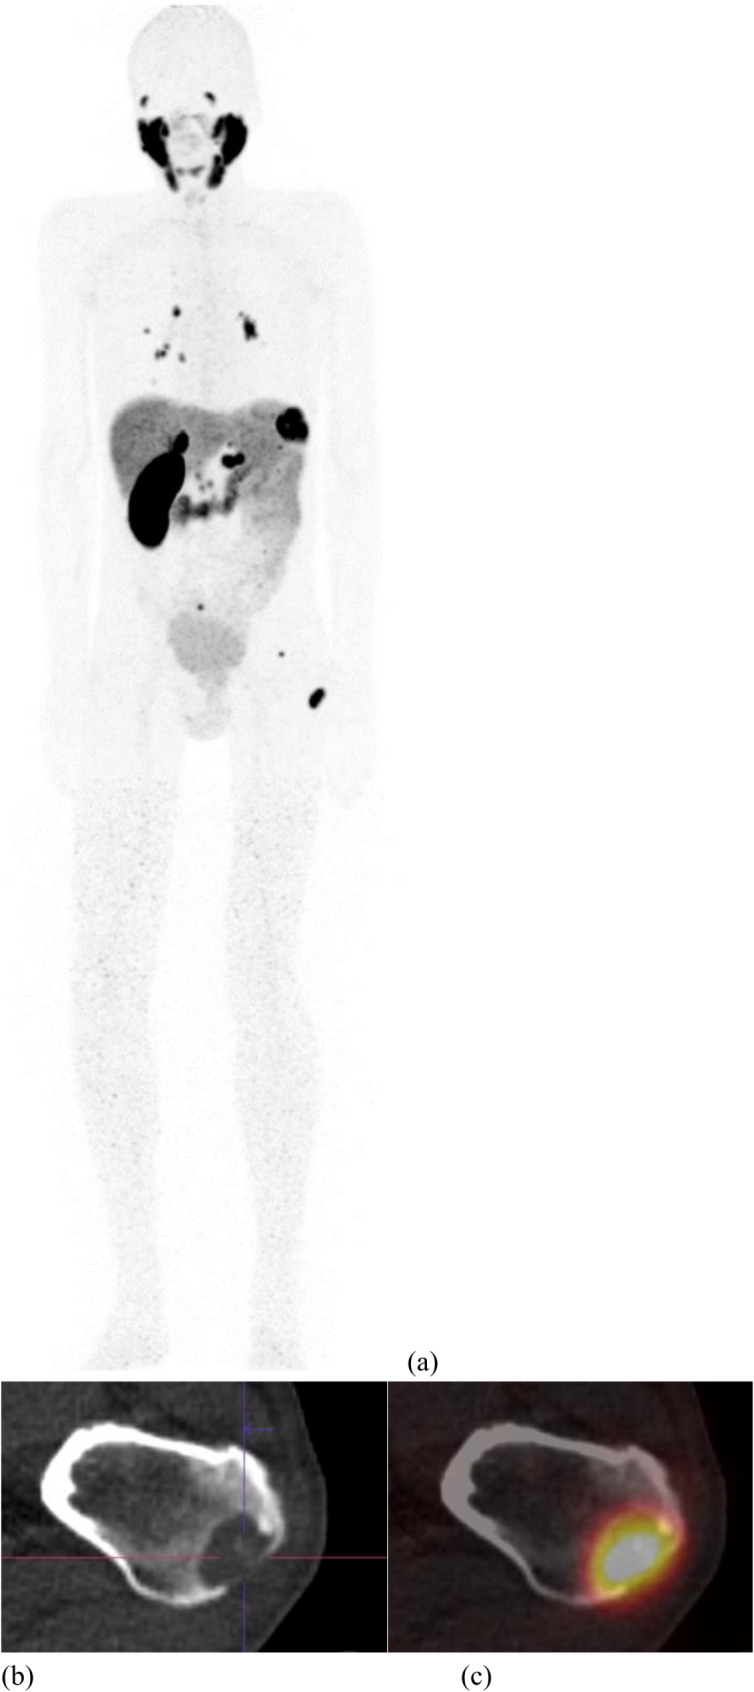

Results: The mean specific binding was 28.9 ± 40.4% for primary renal cancer and 65.0 ± 38.9% for metastasis. Regarding histology, high PSMA expression was depicted in 33.3% of ccRCC, 33.3% of chRCC and 57.1% of papRCC. PSMA was more frequently expressed in primary samples of papRCC histology with renal capsule invasion (p = 0.0286). A higher PSMA-specific binding and a higher number of samples with high PSMA-expression were depicted in metastatic samples. Bone metastasis showed lower binding than other metastatic sites combined (p = 0.0005). The patient suffering from metastatic ccRCC showed high [68Ga]Ga-PSMA-11 uptake on known distant metastases and additional site uncovered.